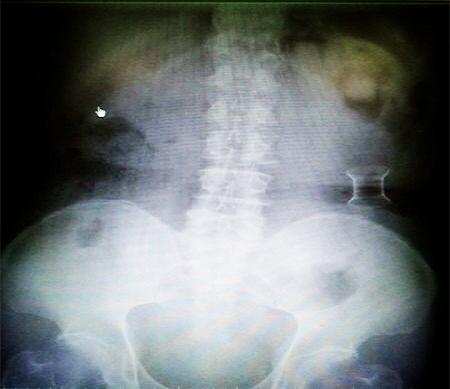

受試患者在結腸端端吻合術中,使用我司新研制產品達到了理想的預期效果。患者術后7天、14天X光片顯影,可降解腸道支架均能按研制設計的預期時間節點保持應有強度,術后21天X光片顯示可降解腸道支架已完全破碎,并排出體外。在整個試驗過程中,病患無任何不良反映,耐受良好。